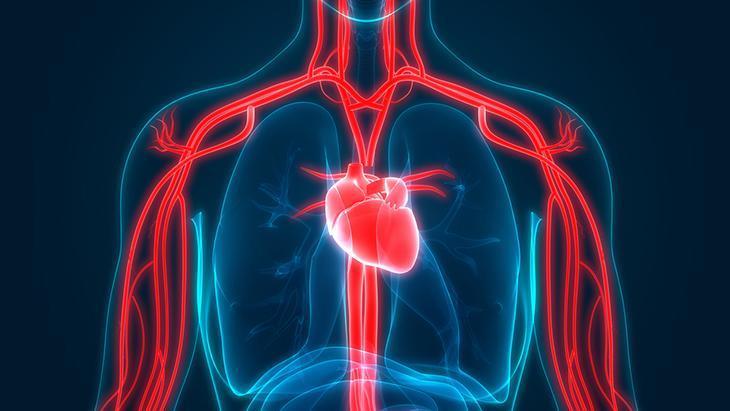

Tüm organlar damar sağlığından etkileniyor

Yaklaşık 1,5 kilogram ağırlığında ve açıldığında 800 metrekarelik yüzeye ulaşan endotel, bu özellikleriyle vücuttaki en büyük organlardan biri olarak tanımlanıyor. Vücuttaki tüm organların damar sağlığından etkilendiğini vurgulayan Türk İç Hastalıkları Uzmanlık Derneği Yönetim Kurulu Başkanı Prof. Dr. Güler, kalp, beyin ve böbrek gibi hayati organların bu etkileri çok daha hızlı gösterdiğini ifade etti.

En küçük tıkanıklık bile risk

Diyabet, sigara ve hipertansiyonun damar yapısına doğrudan zarar verdiğini belirten Prof. Dr. Güler, damar sağlığının korunmasının kritik olduğunu söyledi. Organların sağlıklı şekilde çalışabilmesi için kan akımının düzenli ve kesintisiz olması gerektiğini vurgulayan Prof. Dr. Güler, damarlarda oluşabilecek en küçük tıkanıklıkların dahi ciddi sağlık sorunlarına yol açabileceğine dikkat çekti. Hipertansiyon, diyabet, sigara, obezite ve hareketsiz yaşamın başlıca risk faktörleri olduğunu belirten Güler, bu faktörlerin çoğu zaman birlikte görüldüğünü ve organ hasarı riskini artırdığını söyledi.